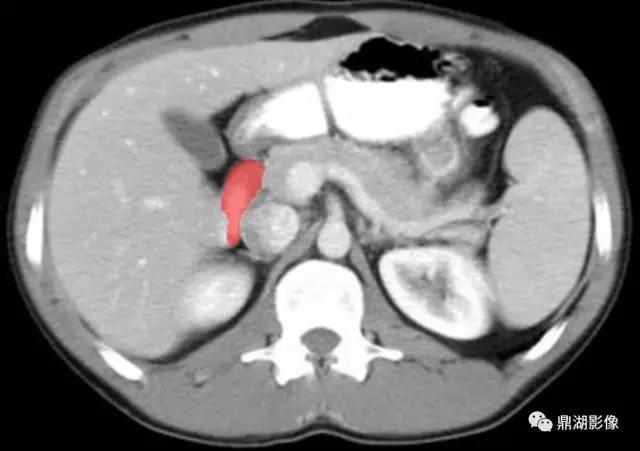

肠系膜上动脉(Superior Mesenteric Artery)

肠系膜上静脉(Superior Mesenteric Vein)